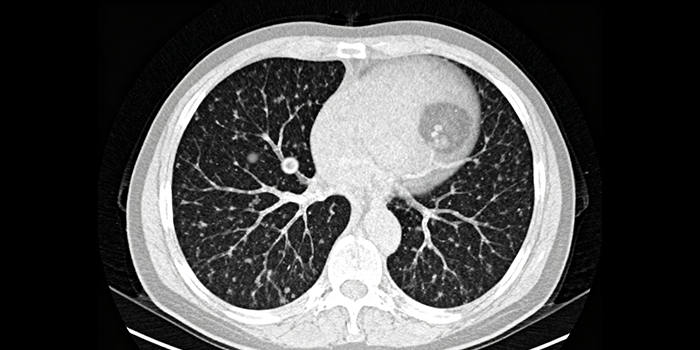

The SONY ILX-LR1 high-resolution sensor offers unprecedented image clarity, allowing even the tiniest lesions or structural changes to be captured clearly. This is of great significance for enhancing the accuracy of diagnosis and the success rate of surgery.

In pathological detection, the 61-megapixel images of SONY ILX-LR1 provide more detailed information, which makes image-based algorithms and artificial intelligence (AI) analysis more effective. For instance, high-definition images can help AI algorithms identify cancer cells or other abnormal cells more accurately.

In endoscopic examinations, due to the sufficient number of pixels, the images captured by SONY ILX-LR1 can be magnified and cropped without losing clarity. Doctors can zoom in on images to examine more closely the minute changes in the intestines or respiratory tract.

The application of SONY ILX-LR1 in the medical testing field has brought about a significant increase in value. Its ultra-high resolution imaging capability provides doctors with the ability to capture more detailed information, allowing even the slightest changes in the lesion site to be clearly displayed, which greatly improves the accuracy and precision of diagnosis.